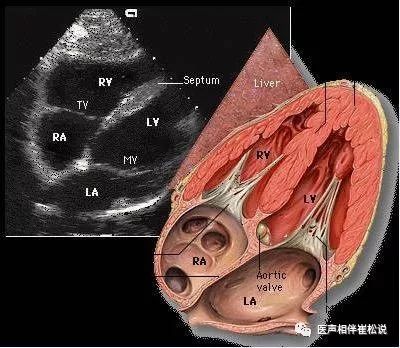

病人收到监护室以后,我马上做了个心超,再结合病史,原来他是一个先天性心脏病,法乐氏三联症术后的病人(法乐氏三联症是指肺动脉瓣狭窄,伴卵圆孔未闭或继发孔型房间隔缺损及右心室肥厚的病人。本病由于右心室排血受阻而发生右心室肥厚、右室流出道进行性梗阻,使右心室、右心房压力增高,心内血液发生右向左分流,病人出现心悸、气短、易劳累、紫绀等症状)。这位患者术后一直还可以,最近刚刚有工作,可能忙了一点,所以在地铁里晕倒被人送到医院。第二天一早,他妈妈就来找我,说他们还是要出院。我说你刚刚经历这个事儿,我们希望再做进一步的检查。妈妈说孩子爸爸很早就离开我们,从小都是我拖他长大,好不容易学校毕业,有一个工作还在试用期,而且他学校刚出来、单位刚进去还没有转正,我们还没有医保,所以我们不想丢了这个工作,也不想让单位知道我们身体有病。我昨天去撒了个谎、请了个假,今天我想让他回去上班。